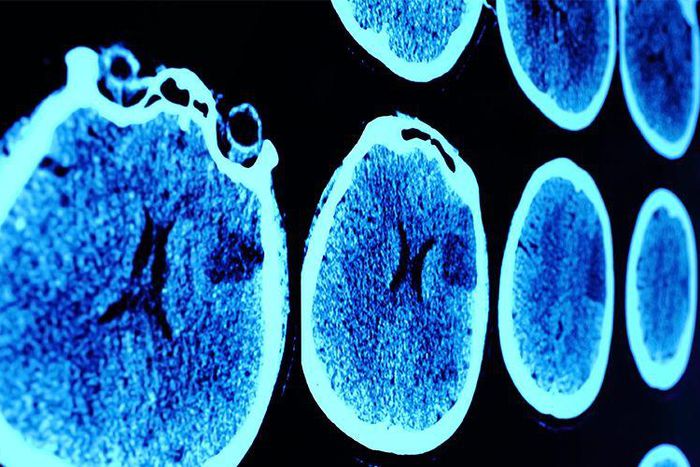

Brain cancer: Thats a really scary term. Luckily, theres a less than 1 percent change youll develop a malignant brain or spinal tumor in your life, according to the <a href="https://www.cancer.org/cancer/brain-spinal-cord-tumors-adults/about/key-statistics.html" id="f45bfc67-d3f5-36ec-ab00-a2ebdee8638c"> American Cancer Society </a> . Still, the <a href="https://www.cancer.org/cancer/brain-spinal-cord-tumors-adults/about/key-statistics.html" id="7c40b522-55c3-339e-a5f7-6f36a29d098b"> ACS </...

Over time, brain cancer can impact surrounding brain cells to seriously compromise brain function. And while that's true of all brain tumors, malignant or benign, cancerous tumors are more likely to spread throughout the brain, and quickly, according to Hormigo. That's why malignant tumors require aggressive treatments, typically including surgery, radiation, and/or chemotherapy , she says.

The thing is, your doctor doesn't routinely screen for brain cancer, and, currently, no widely agreed upon screenings even exist, according to the American Cancer Society . So it's up to you to keep tabs on your health and understand the most common brain cancer symptoms. If you have any symptoms that could indicate a brain tumor, you should go to your primary care doctor or internist as soon as possible, says Hormigo. They can guide you to the right specialist.